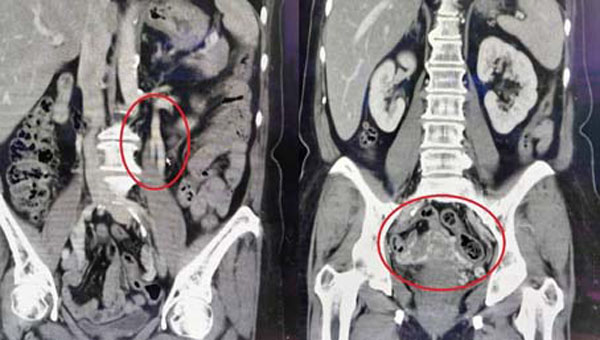

在排除可能导致骨盆腔疼痛的疾病后,仍找不出异常原因的病人,可考虑接受超音波或电脑断层检查骨盆腔内静脉是否扩张。若为骨盆腔郁血症候群,透过电脑断层可发现生殖器官旁边出现大量静脉,如同骨盆腔里的静脉曲张。